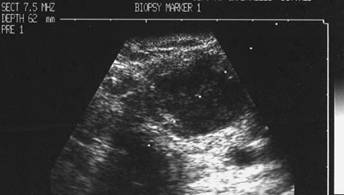

Lobul drept, proiectie trasversala si longitudinala.

Femeie de 29 ani. Nodul de consistenta dura in lobul

drept si istm.

Ecografia: nodul cu margini difuze in lobul drept si istm, care deformeaza

conturul anterior al glandei, structura parenchimatoasa, neoomogena, hipoecogena.

Prezenta de linfonoduli laterocervicali.

Citoaspiratia: carcinom papilar.

Examen histologic: carcinom papilar plurifocale varianta foliculara.